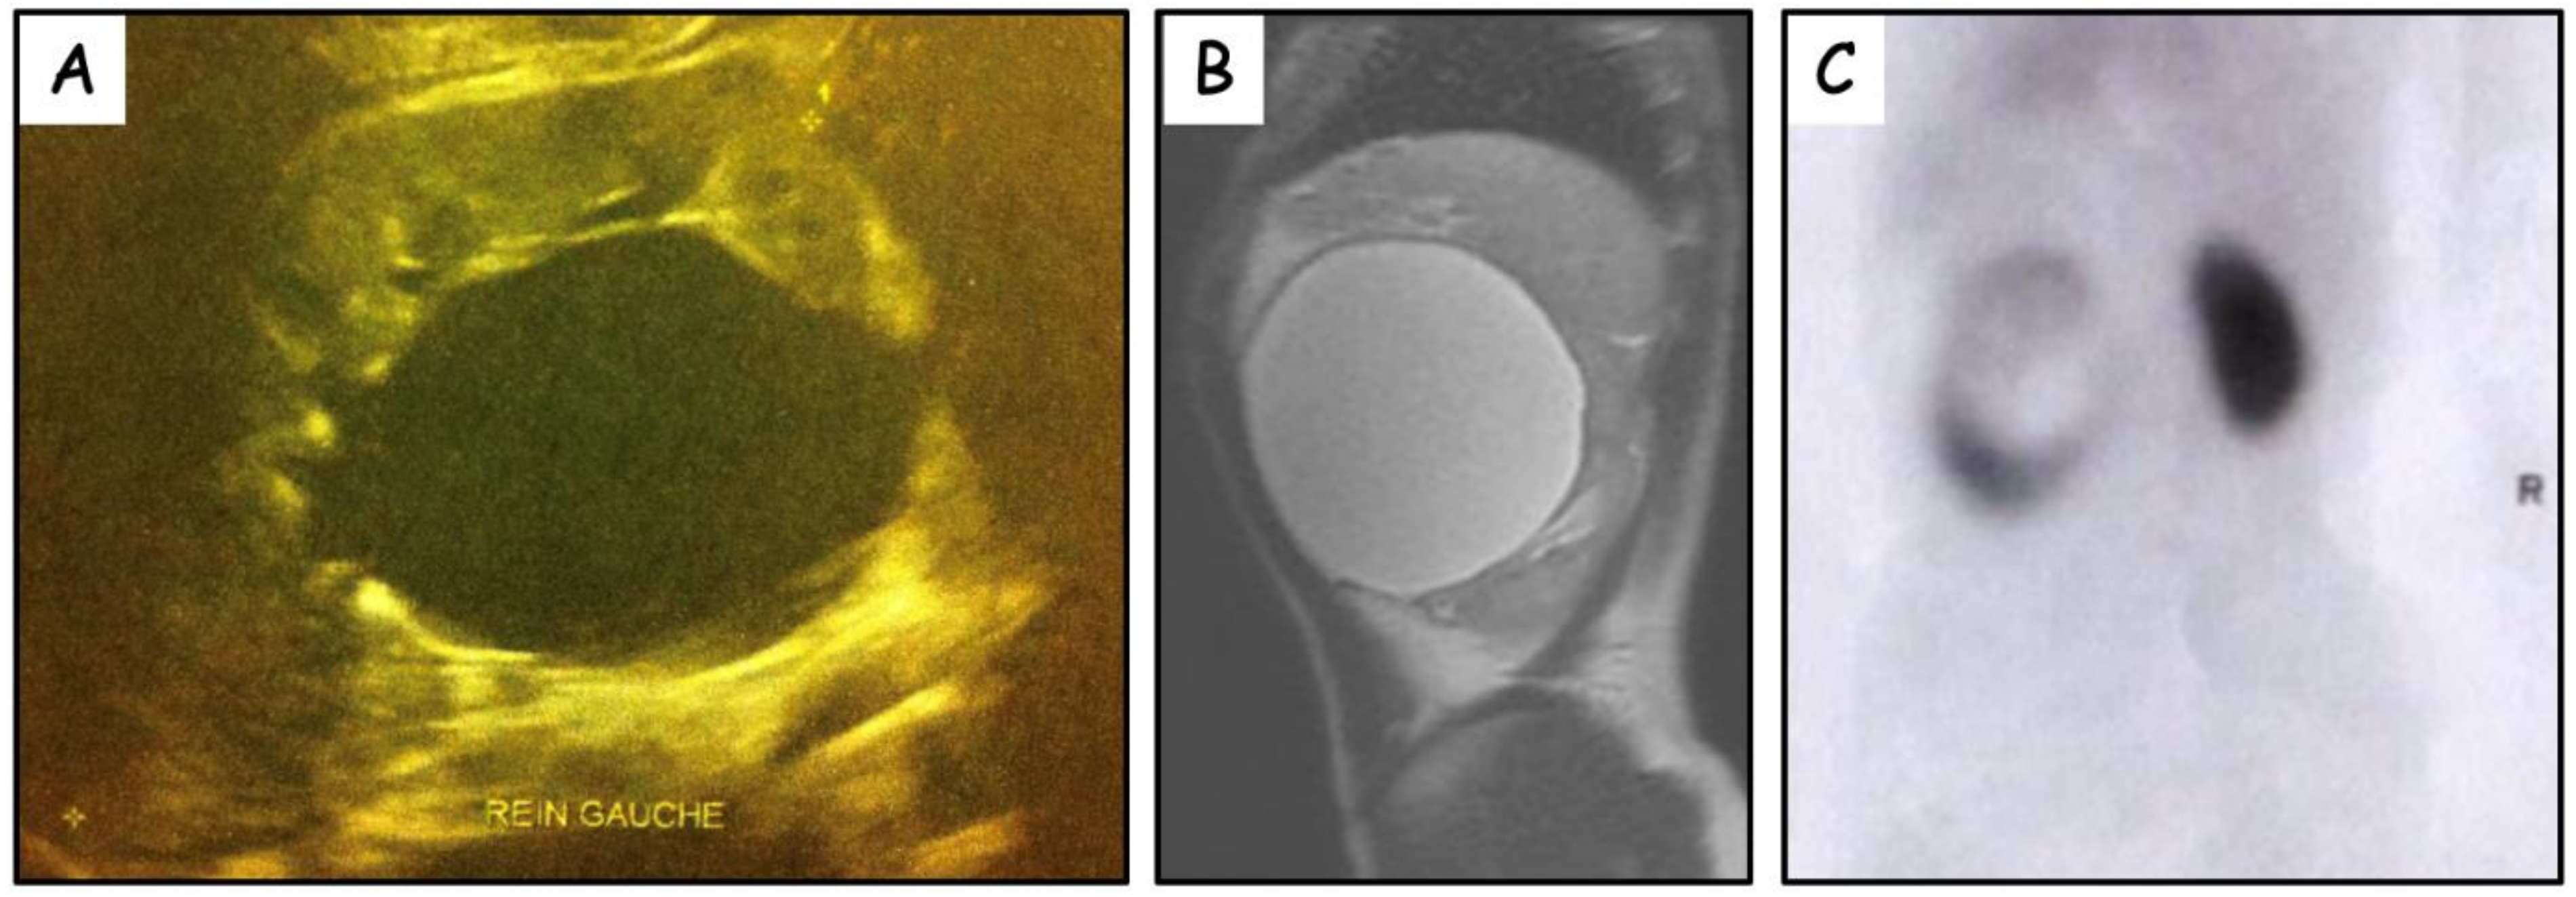

3. Results